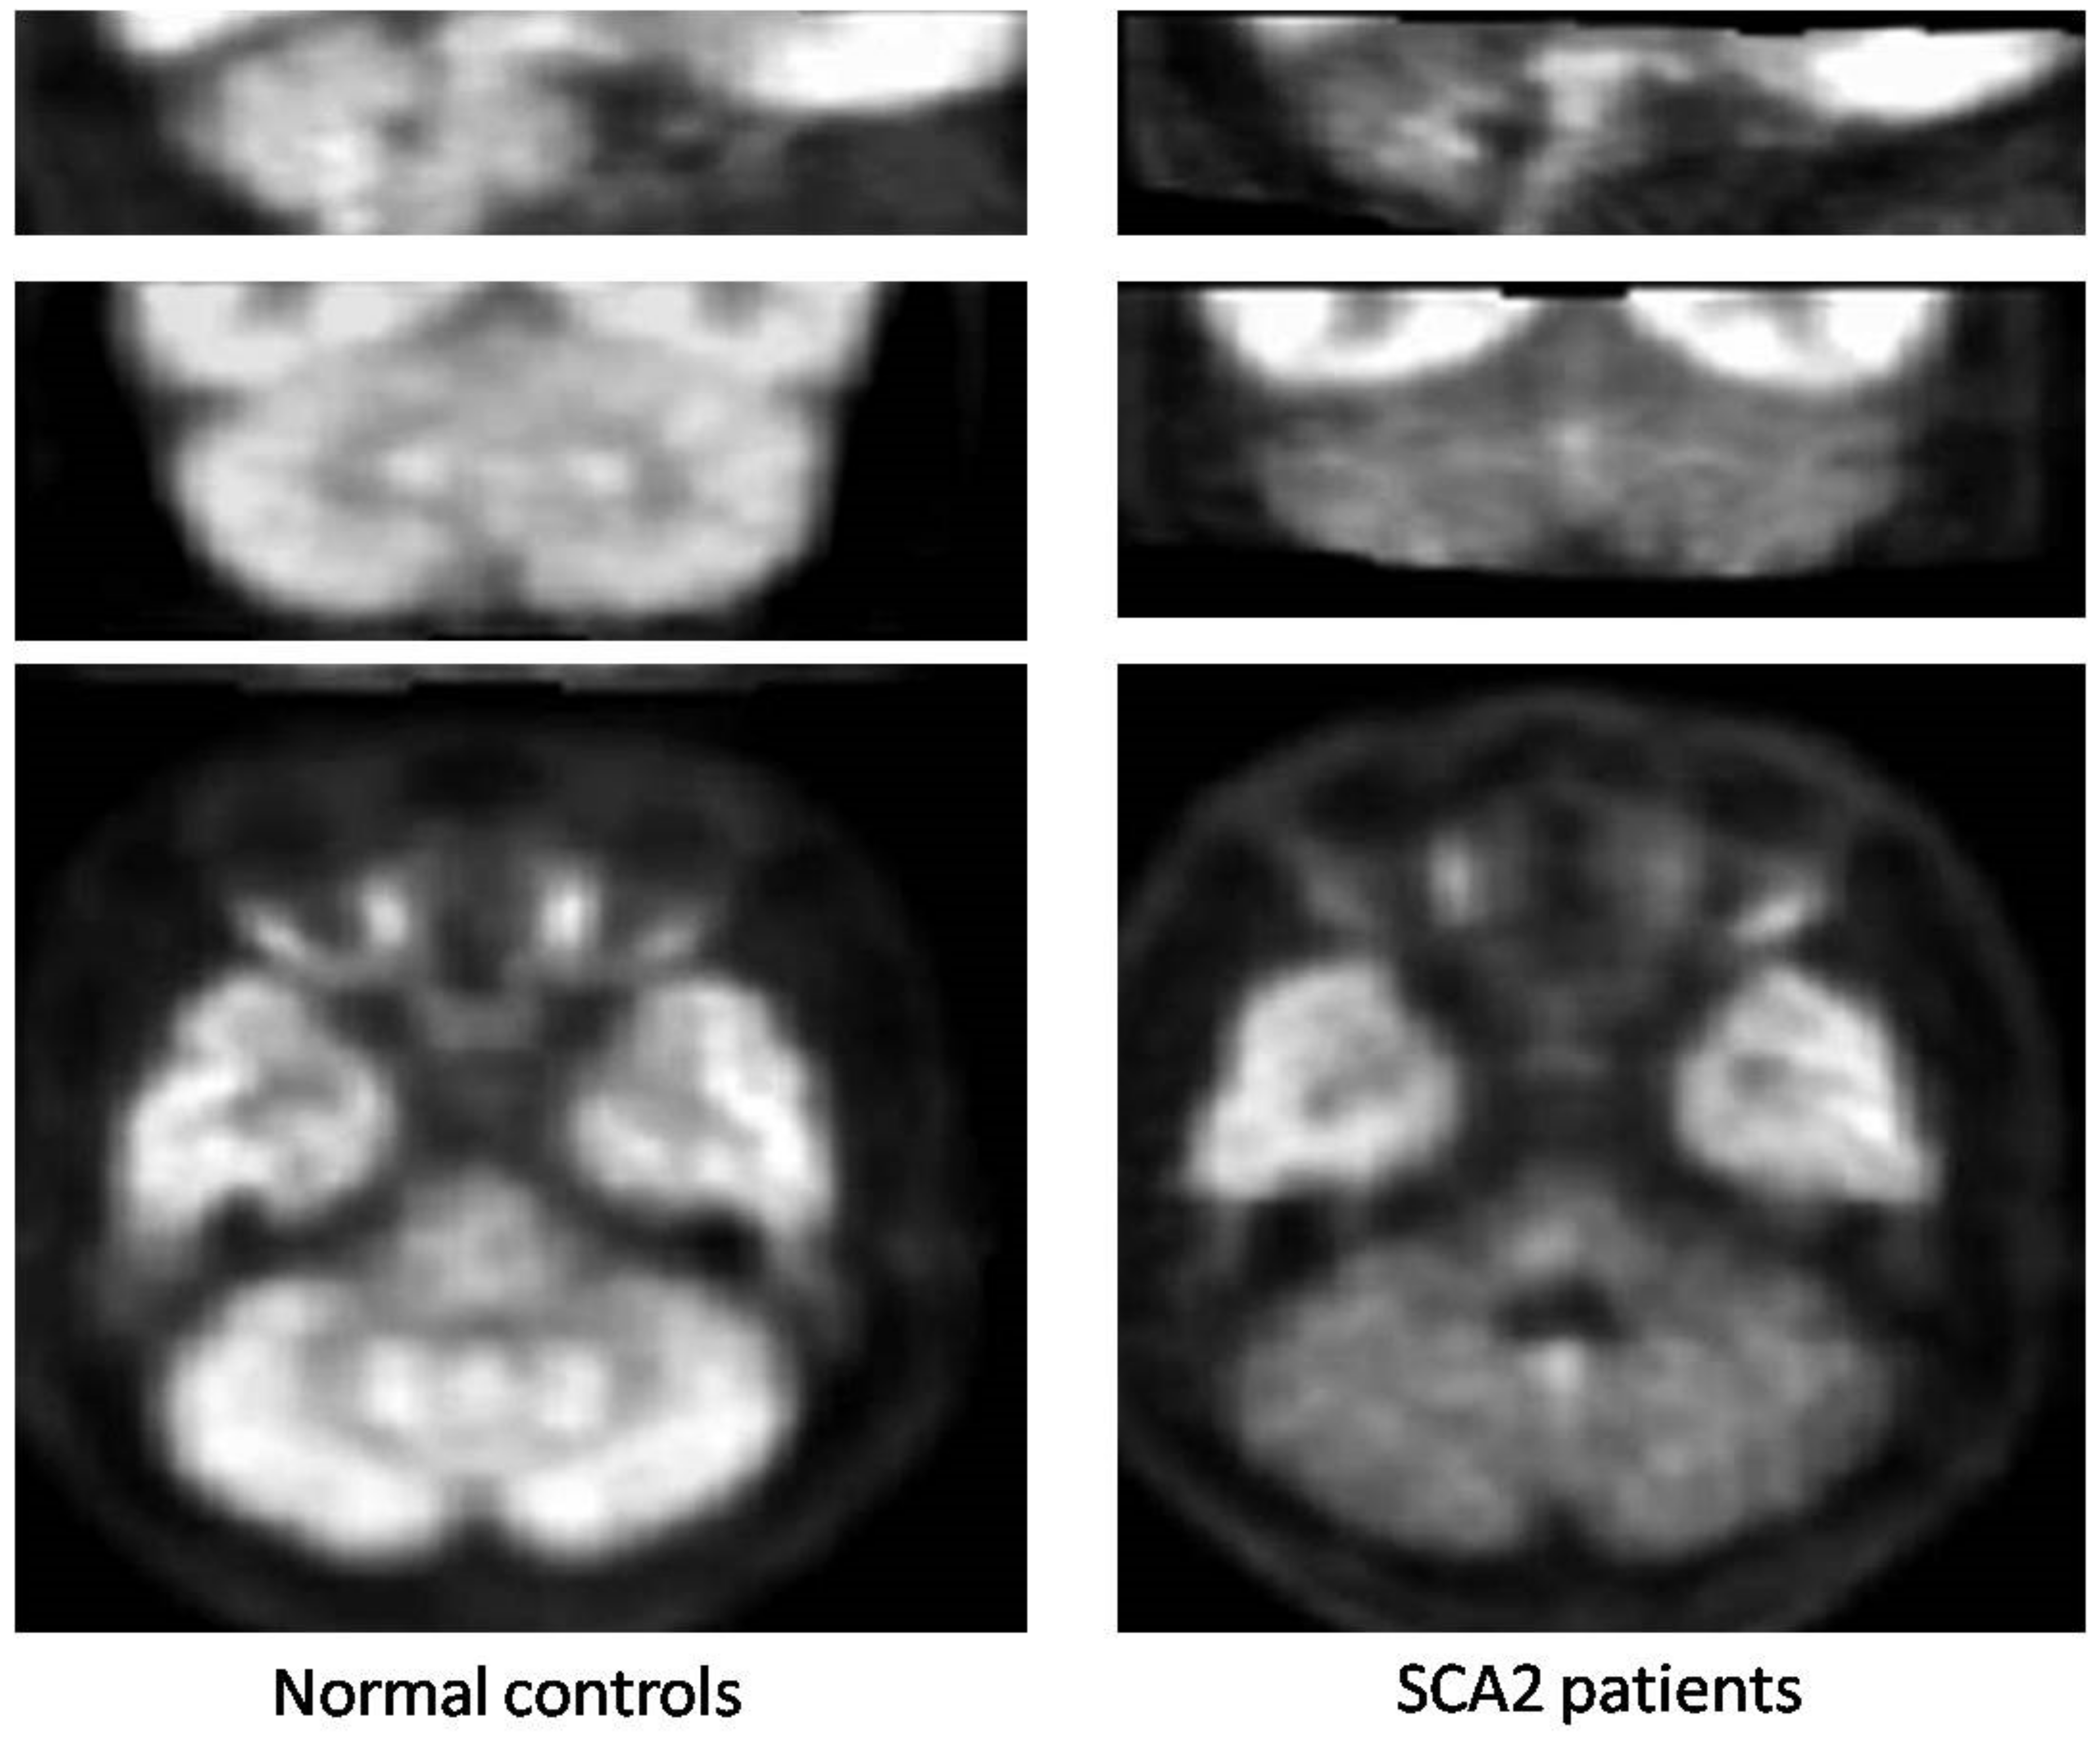

- Mascalchi, M.; Marzi, C.; Giannelli, M.; Ciulli, S.; Bianchi, A.; Ginestroni, A.; Tessa, C.; Nicolai, E.; Aiello, M.; Salvatore, E.; et al. Histogram analysis of DTI-derived indices reveals pontocerebellar degeneration and its progression in SCA2. PLoS ONE 2018, 13, e0200258. [Google Scholar] [CrossRef]